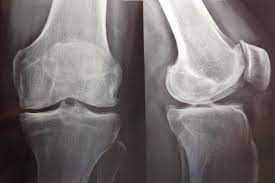

En este estudio poblacional, una tasa de pérdida de peso lenta a moderada, pero no rápida, inducida por medicamentos contra la obesidad se asocia con un menor riesgo de mortalidad por todas las causas en personas con sobrepeso u obesidad y artrosis de rodilla o cadera. Arthritis Rheumatol. 6 de diciembre de 2023